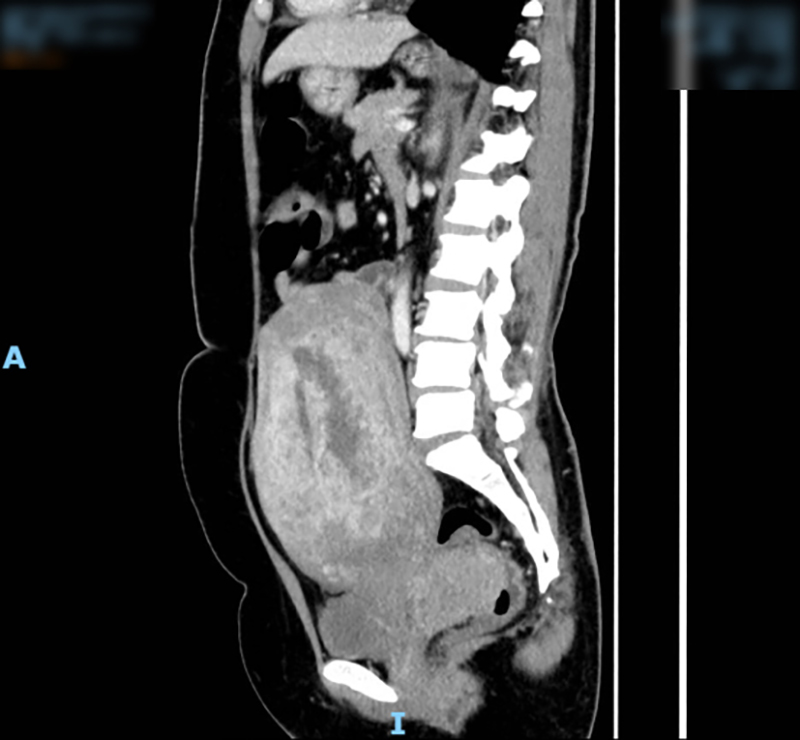

患者術前CT影像

在MDT討論中,醫生考慮患者的子宮內膜癌直腸轉移為惡性腫瘤,子宮直腸窩腫物侵犯至直腸粘膜層,與陰道后壁關系致密,伴腹腔多發淋巴結轉移,需要實施“全子宮+雙附件+手術分期+減瘤術”將腫瘤整塊切除,盡量減少破瘤而入。同時,還要將直腸、直腸窩腫物一并整塊切除,并行預防性造瘺,待直腸吻合口愈合后還納。